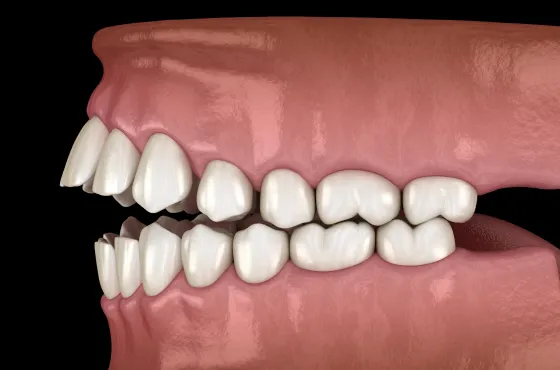

歯周炎:骨が溶けはじめる中~重度段階

歯肉炎を放置すると、炎症はさらに深い部分――歯を支える組織(歯周組織)へと広がり、「歯周炎」へと進行します。

この段階になると、歯を支える骨(歯槽骨)が細菌によって徐々に破壊され始め、歯のぐらつき、噛むと痛い、膿の排出、口臭の悪化など、目に見える症状が現れます。

初期の歯周炎では、歯と歯ぐきの間に「歯周ポケット」という深いすき間が形成されます。

このポケット内は酸素が少なく、歯周病菌にとって繁殖しやすい環境。細菌が増え続けることで炎症が慢性化し、やがて歯を支える骨を溶かしていきます。中等度に進行すると、歯を押すと動く・噛むと痛い・膿がにじむといった症状が現れ、日常生活にも支障をきたすようになります。

さらに悪化すると、歯槽骨の半分以上が失われる「重度歯周炎」に移行します。

支えを失った歯は大きく動揺し、最終的に自然に抜け落ちるケースもあります。この段階では、失った骨を再生するための歯周組織再生療法など、外科的な治療が必要になることもあります。

放置すると、炎症は歯ぐきの奥深くに広がり、「軽度歯周炎」へ進行します。

歯を支える骨(歯槽骨)が少しずつ溶け始め、歯と歯ぐきの間に「歯周ポケット」と呼ばれるすき間ができるのが特徴です。このポケット内は酸素が少なく、歯周病菌が繁殖しやすい環境のため、炎症がさらに進行していきます。

「中等度歯周炎」になると、歯槽骨の破壊が進行し、歯のぐらつきが現れ始めます。噛むと痛い、膿が出る、口臭が強くなる、歯ぐきが下がって歯が長く見える――といった症状が増えていきます。この段階では通常のクリーニングでは改善が難しく、「歯周外科治療」などの外科的なアプローチが必要になるケースもあります。

そして「重度歯周炎」に進行すると、歯槽骨の大部分が溶け、歯が支えを失ってグラグラの状態に。

歯ぐきから膿が出たり、強い口臭を伴ったりすることも多く、最終的には歯が自然に抜け落ちてしまうこともあります。ここまで進行すると、失われた骨や歯周組織を再生させる「歯周組織再生療法」など、より高度な治療が必要となります。